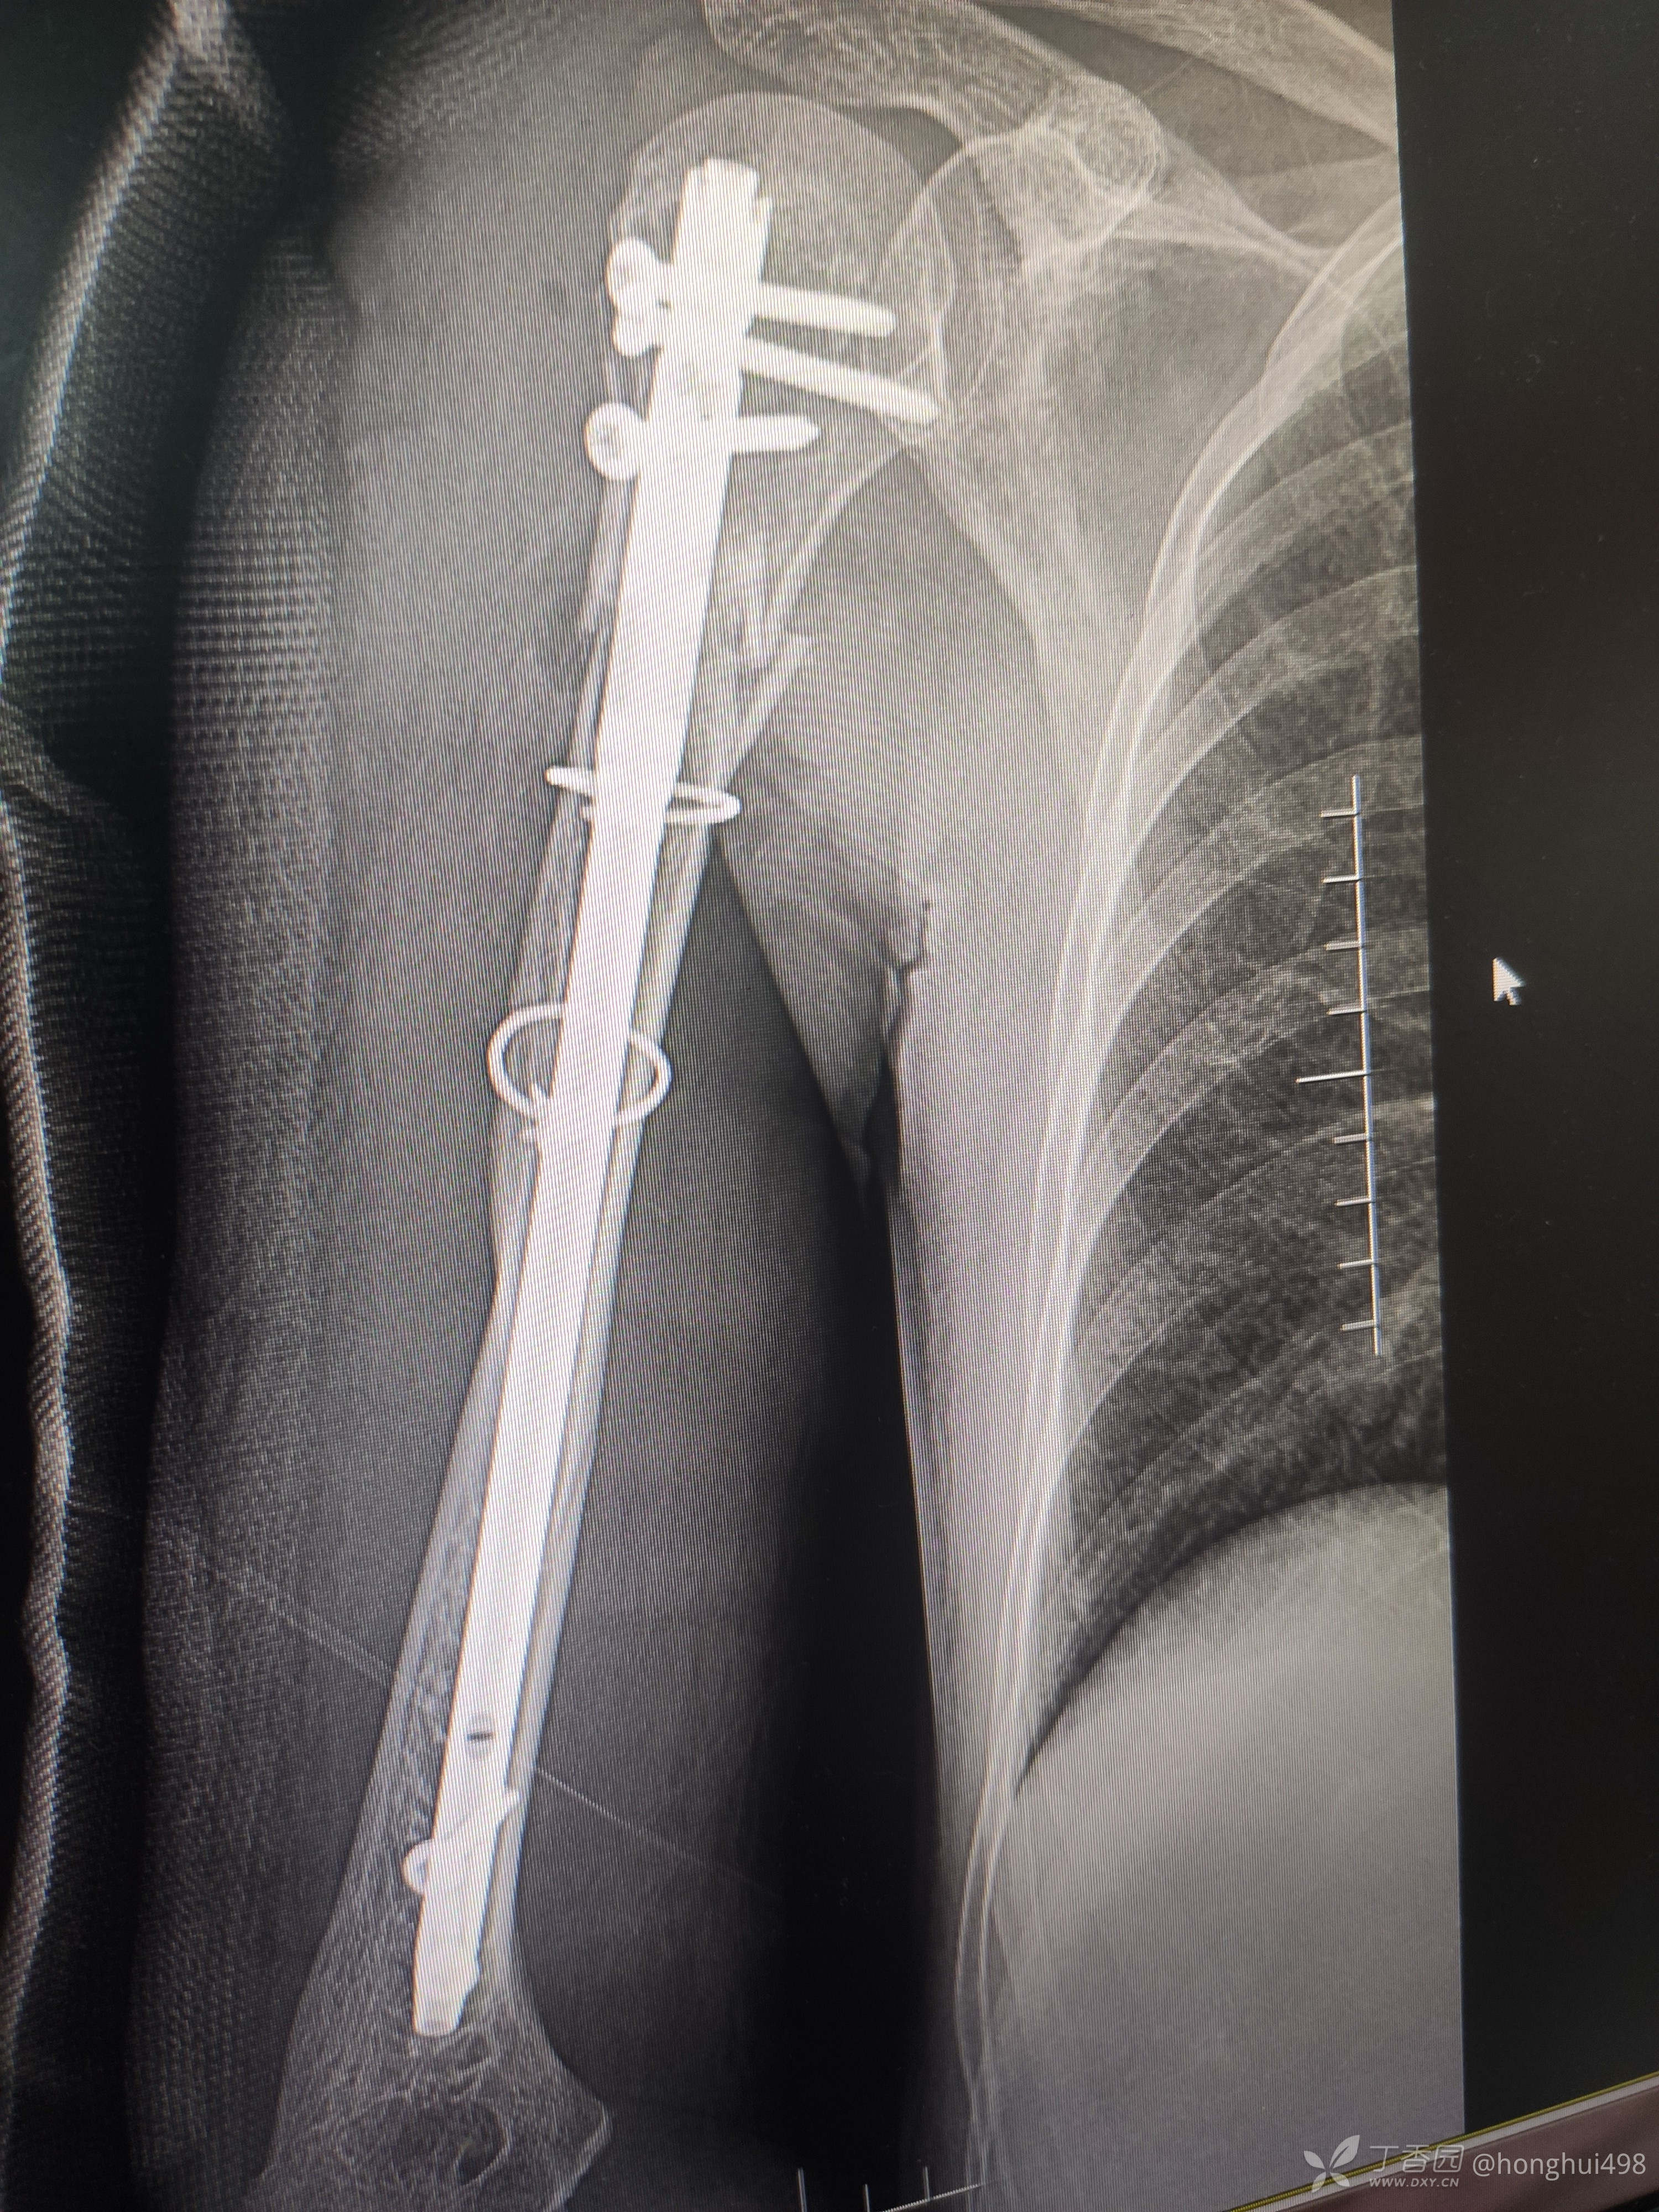

男性患者,62岁,摔倒致伤,入院诊断右肱骨骨折。麻醉下行肱骨骨折有限切开复位髓内钉+钢缆固定。

肱骨髓内固定做得比较少,但是手术还是顺利,此例患者你们如何选择固定方式?欢迎讨论